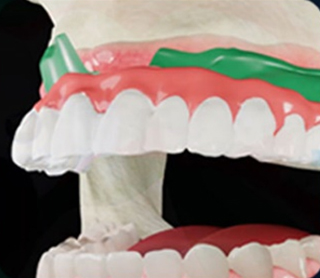

• 3D 컴퓨터 모의시술 및

보철물 디자인

유도 가이드 제작